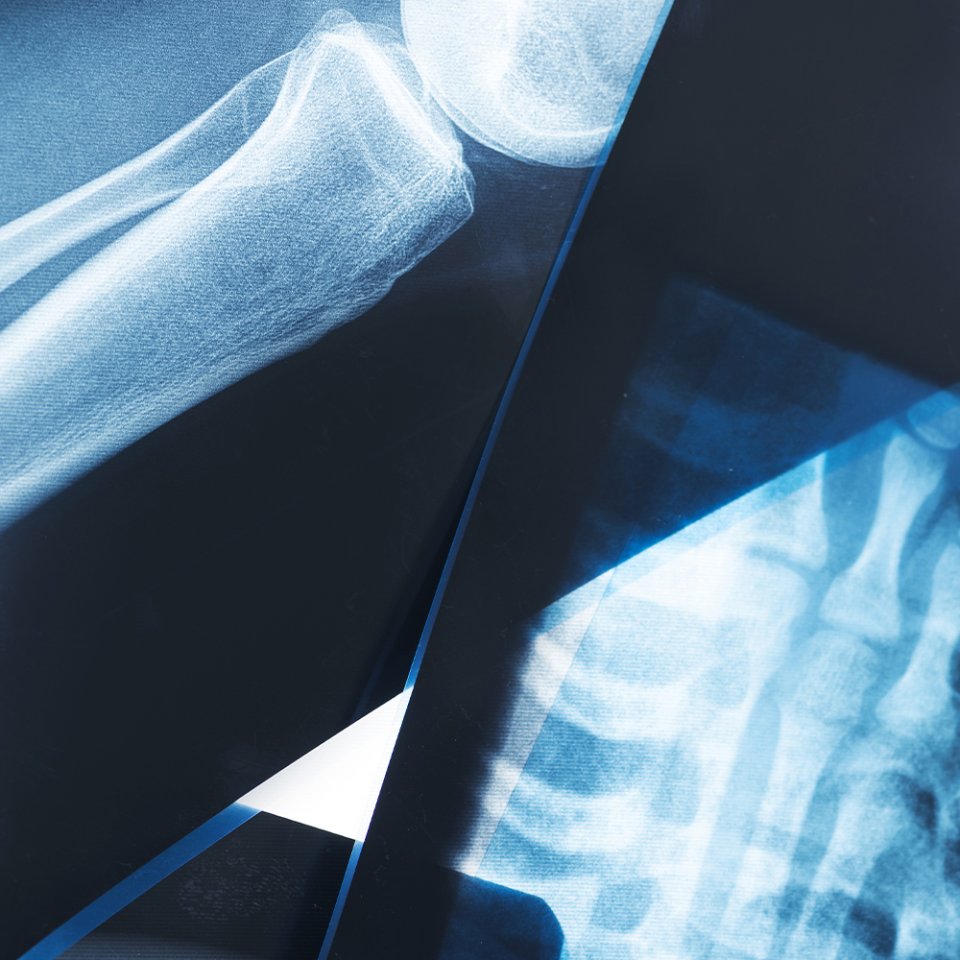

What is Trauma & Fracture Surgery?

Trauma and fracture surgery focuses on the treatment of broken bones, dislocations, and complex injuries caused by accidents, falls, or sports-related trauma. These procedures aim to restore bone alignment, ensure proper healing, and help patients return to daily activities as quickly and safely as possible.